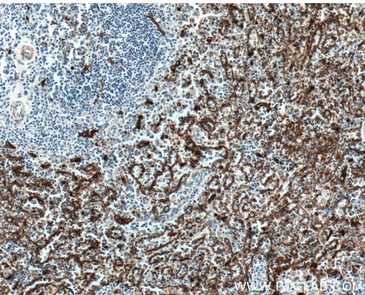

| Positive IHC detected in | human spleen tissue, human heart tissue Note: suggested antigen retrieval with TE buffer pH 9.0; (*) Alternatively, antigen retrieval may be performed with citrate buffer pH 6.0 |

| Immunohistochemistry (IHC) | IHC : 1:400-1:1000 |